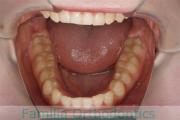

- ≫治療前

上顎

下顎

前歯の関係など

- ≫治療後